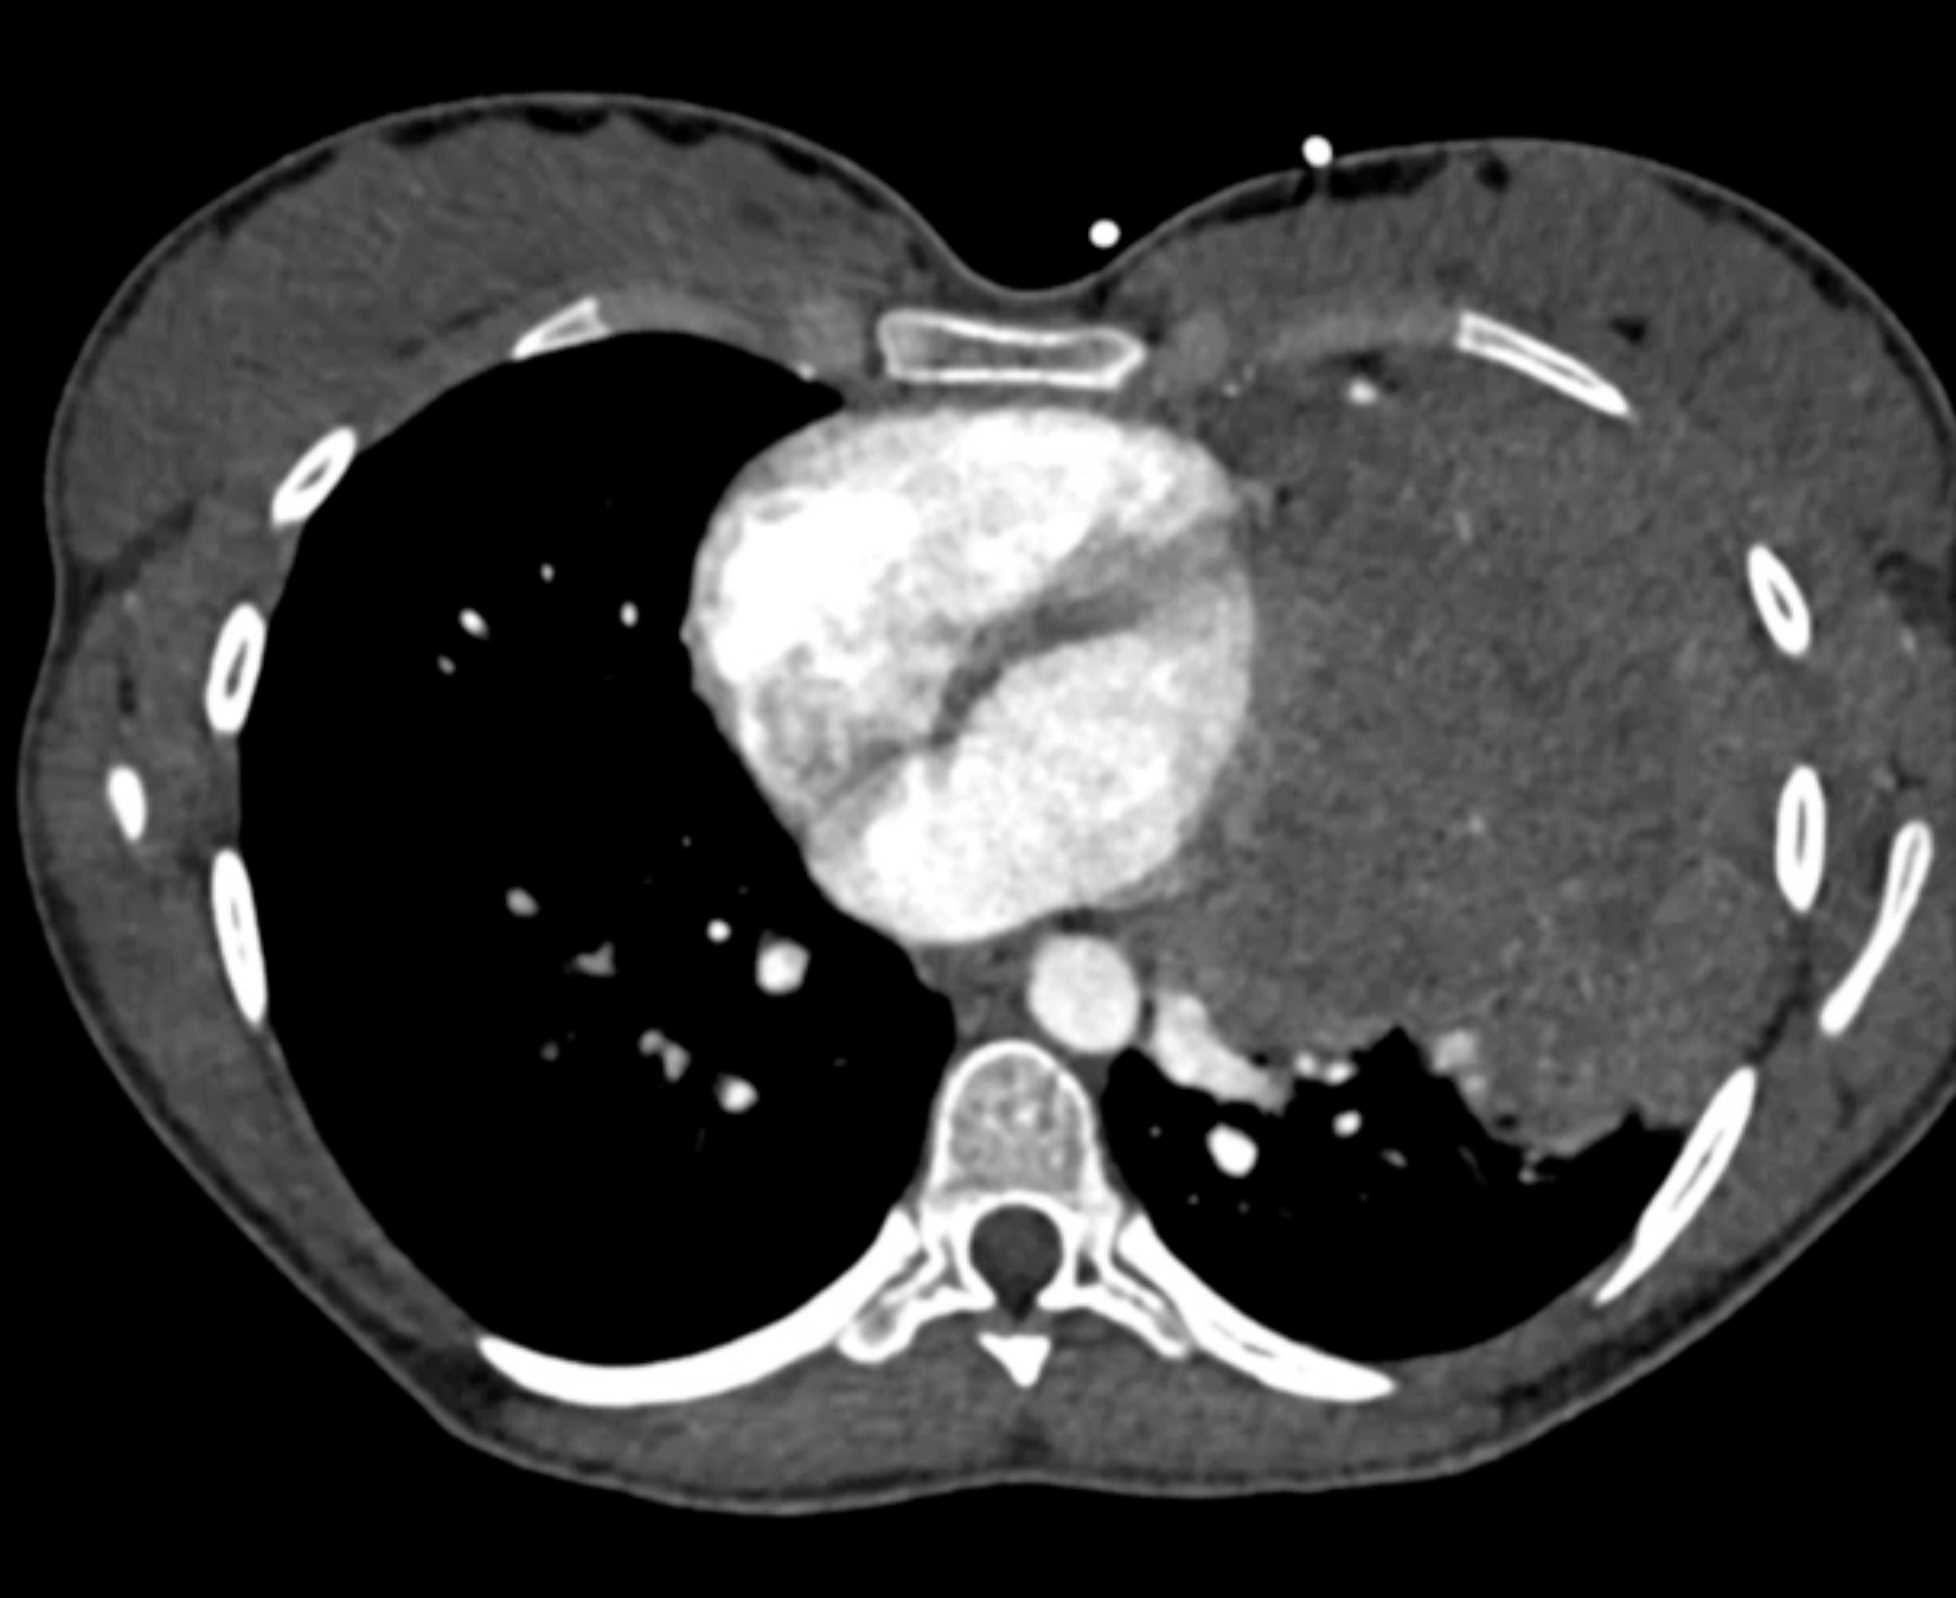

Subtle Adenocarcinoma Pancreas